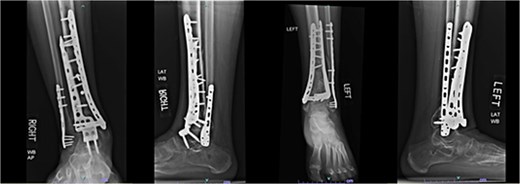

One year after the initial surgery, the left leg healed without any complications. However, the right leg developed nonunion through the distal tibia, along with posttraumatic arthritis. As a result, the patient underwent a right ankle fusion. Additionally, 2.5 years after the index surgery (1.5 years after the ankle fusion), the patient required removal of the right lateral fibular plate due to painful hardware. Six months later (3 years post-index surgery), the patient then underwent subtalar fusion due to post-traumatic arthropathy and ongoing pain (Fig. 2).

Radiographs of patient 1 obtained 3 years after the index procedure, including AP view of the left ankle and lateral and oblique views of the right ankle following subtalar fusion.